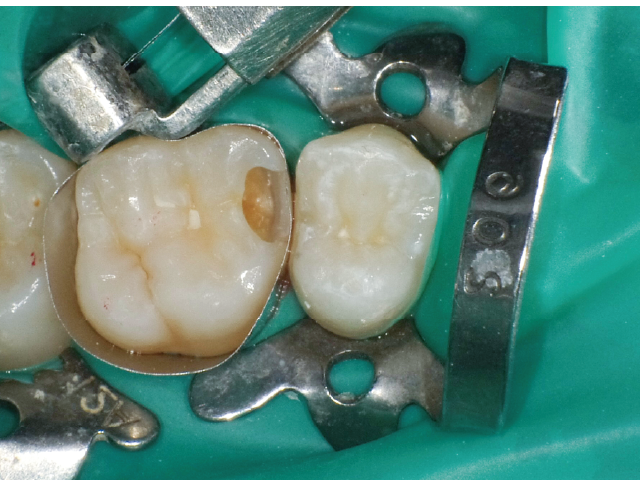

①窩洞形成段階(図1~7)

本症例では、ダイヤモンドの微粒子でコーティングされたエアースケーラーチップを窩洞形態の仕上げに使用。隣在歯の誤切削を防止し、エナメル質の切削断面を歯肉側窩縁までなめらかになるよう仕上げました。

本チップは切削時にストレスが少ない穏やかな振動のエアースケーラー専用のダイヤモンドチップで、切削部となる半球形状の面にのみダイヤモンド砥粒がコーティングされており、背面平坦部は隣在歯を削らないよう平滑になっています(図8、9)。チップの屈曲角度は110°に設定され、窩洞へのアクセスが容易な形状となっています。S67D(アングルの外側)、S68D(アングルの内側)チップは半球状の切削部位が設定され、臼歯部の近遠心両側の窩洞形成に使用が可能です。本症例では、左上6近心隣接面部の窩洞であったため、アングルの外側に半球状の切削部位が設定されている「S67D」を使用しました。これらの器具を使用することにより、頬舌側の隅角部歯質を温存した最小限の規模で窩洞形成を終了、防湿操作および隔壁の設置に移行することができました。